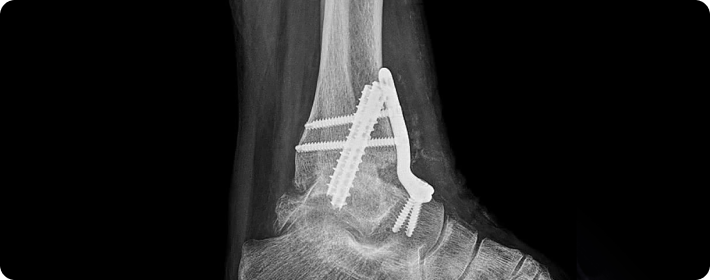

골절고정술

부러진 뼈를 정확한 위치에 맞춘 뒤, 금속판, 나사, 핀 봉 등을 이용해 단단히 고정하여 뼈가 바르게 치유되도록 돕는 수술입니다. 뼈의 정렬을 유지하고 회복을 촉진하는 데 중요한 치료입니다.